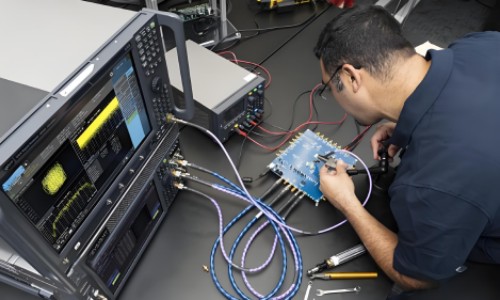

NexGen 7T fMR(左)内有一个7特斯拉超导电磁铁。该机器的分辨率高于标准的3T医院扫描仪右)和传统7T成像仪(中)